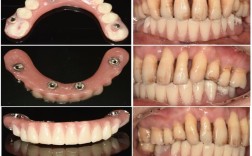

| 即刻负重(特殊情况) | 骨质良好,初期稳定性高,医生评估后 | 2-3个月(临时冠) | 2-3个月(临时冠),3-6个月(永久冠) |

A:可以,对于前牙种植,若患者对美观要求较高,医生可在骨结合期间制作临时牙冠(如树脂临时冠),临时牙冠主要起美观和维持牙龈形态的作用,强度较低,不能用于咀嚼硬物,待骨结合完成后,再更换为永久性牙冠(如全瓷冠、金属烤瓷冠等)。